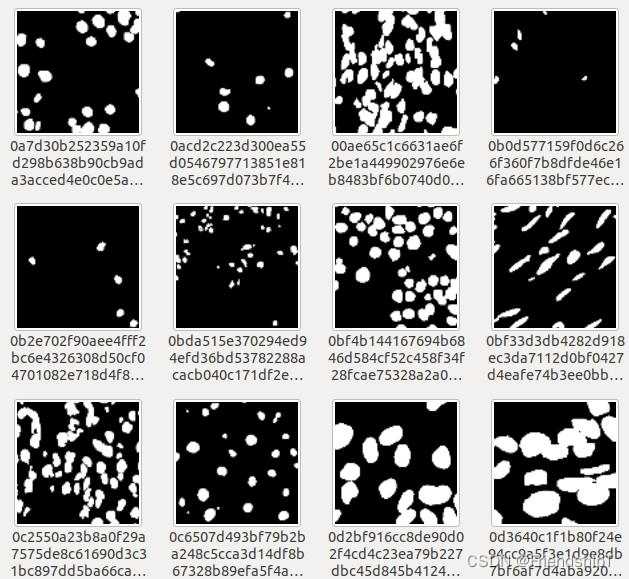

准备数据集

- mask图